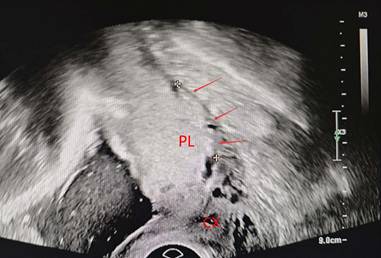

Ultrasound (US) and magnetic resonance imaging (MRI) have shown high diagnostic performance in the detection of PAS[17-19]. Ultrasound serves as the primary diagnostic tool for PAS; however, current clinical sonographic criteria are primarily validated for anterior PAS cases complicated by placenta previa. When the placenta invades the posterior uterine wall, the diagnostic accuracy of prenatal ultrasound in detecting characteristic signs remains uncertain[17, 18, 20]. Dellapiana et al. reported that the application of standard sonographic criteria results in a low antenatal detection rate for posterior PAS[21]. For optimal ultrasound diagnosis of posterior PAS, the recommended gestational window for initial screening is between 25 and 28 weeks. This timing is advantageous because: the uterine wall and placental architecture are more clearly visualized at this stage, the amniotic fluid-to-fetal size ratio is more favorable, and the posterior implantation site becomes more accessible for evaluation[22]. The ultrasound markers of PAS include: (1) Loss or irregularity of the hypoechoic area between the uterus and placenta, the 'retroplacental clear zone' (Figure 1), (2) Myometrial thickness <1mm, (3)placental lacunae with high velocity flow (>15cm/s) (Figure 2), (4)Thinning or interruption of the uterine serosa-bladder wall interface, (5) Placental bulge, (6) Exophytic mass,(7) Subplacental and/or uterovesical hypervascularity, (8) Loss of vascular arch parallel to the basal plate and irregular intraplacental vascularization (Figure 3)[3, 23]. After excluding the two bladder line-dependent criteria, the following four key sonographic features were consistently observed in the posterior placental region: loss or irregularity of the hypoechoic area between the uterus and placenta, myometrial thickness <1mm, placental lacunae with high velocity flow (>15cm/s), and Loss of vascular arch parallel to the basal plate and irregular intraplacental vascularization[22]. Many authors have adopted a two-criteria system in their articles: PAS is diagnosed when there are two or more ultrasonic signs present[22, 24]. The two-criteria system has a high sensitivity (60.0%), specificity (98.9%), and positive predictive value (85.7%). Moreover, when using a single criterion or the optimal criterion, there is no improvement in the maternal outcomes of true positive and false negative cases, which confirms the reliability of the two-criteria system[22]. A retrospective study has found that the sensitivity of ultrasound in detecting anterior PAS is as high as 81 - 93%[18]. Other studies have also validated this discrepancy. The ADoPAD (Antenatal Diagnosis of Placental Attachment Disorders) Study Group reported that prenatal ultrasound detected 92% of all anterior PAS cases, which was significantly higher than the 62% detection rate for posterior PAS[11]. The detection rates of PAS in anterior and posterior placentas were reported by Pilloni et al. as 89.7% and 50% respectively, under the application of the two - criteria system[24]. However, in a recent study, after excluding patients with placenta previa, only 30% of posterior placenta PAS cases were diagnosed through prenatal ultrasound screening. This suggests that compared with anterior PAS, ultrasound examination has lower sensitivity for posterior PAS[21]. An independent evaluation of the sensitivity of individual ultrasound signs for pathologically confirmed posterior and anterior PAS was conducted. The sensitivities of retroplacental lacunae, vascular congestion, myometrial thinning, and absence of hypoechoic areas in detecting posterior wall PAS ranged from 24% to 42%. However, multiple studies have demonstrated that the absence/irregularity of the retroplacental clear zone shows the highest sensitivity and negative predictive value for posterior placenta accreta - comparable to or even exceeding that of the dual-criteria system. These findings confirm the diagnostic importance of this specific criterion for posterior placenta accreta, while other criteria exhibit significantly lower sensitivities compared to the dual-criteria system[22, 24]. This divergence primarily stems from hemodynamic differences, as the posterior uterine wall's lower segment demonstrates greater vascularity compared to the anterior wall. Sonographically, the retroplacental clear zone shows better echogenic contrast with posterior placental positioning than with anterior implantation. Consequently, when placental invasion disrupts the retroplacental clear zone's integrity, sonographic abnormalities become more detectable on the posterior uterine wall. This diagnostic advantage is most evident between 26 and 28 weeks of gestation[24]. In summary, ultrasound demonstrates suboptimal sensitivity for detecting posterior PAS. As the first-line imaging modality, its diagnostic performance is limited by three key factors: (1) operator-dependent variability, (2) reduced efficacy in obese patients, and (3) poor detection of posterior placental invasion. These limitations collectively compromise both the accuracy and clinical utility of ultrasound for posterior PAS diagnosis. Furthermore, current research on posterior PAS remains constrained by small sample sizes, highlighting the need for larger-scale studies to validate existing findings[22].

Figure 3

irregular intraplacental vascularization of posterior placenta(arrow) PL, placenta. CX, cervix.